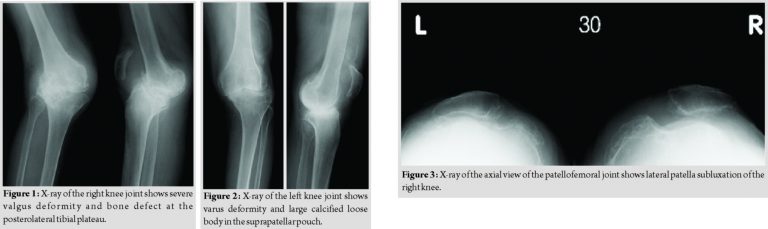

A plain radiograph of the right knee showed severe valgus and recurvatum deformity with a severe bone defect at the posterolateral tibial plateau (Fig. 1), while that of the left knee showed varus deformity with a large calcified loose body in the suprapatellar pouch (Fig. 2). Moreover, lateral patellar subluxation of the right knee was evident (Fig. 3). The anatomic femorotibial angle was 140at the right and 180at the left (the so-called windswept deformity) (Fig. 4). All other joints were normal.

After admission, bed rest and arthrocentesis relieved her knee pain. A culture of the synovial fluid was negative. An examination of the nerve conduction velocities in her legs showed us that she had severe sensory neuropathy of the bilateral lower limbs. Based on her medical history, we believed that this patient had developed bilateral neuropathic arthropathies caused by lumbar spinal canal stenosis. Because she could not walk due to instability, we decided to perform a staged bilateral TKA. We performed TKA of the right knee first because its deformity was more severe. We chose a rotating hinge prosthesis (Modular Rotating Hinge; Stryker, Mahwah, NJ, USA) and performed the procedure using a medial parapatellar approach. Modular stems were used both on the tibial and femoral implants. The procedure included autologous bone grafting and metal augmentation for tibial bone loss and patella replacement and lateral retinaculum release for patella subluxation.